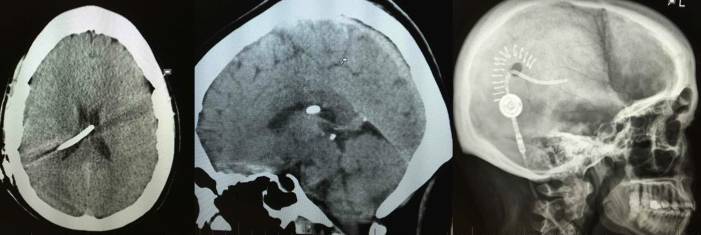

Внутричерепная гипотензия: КТ-исследования и их интерпретация

Раздел: Образы вокруг